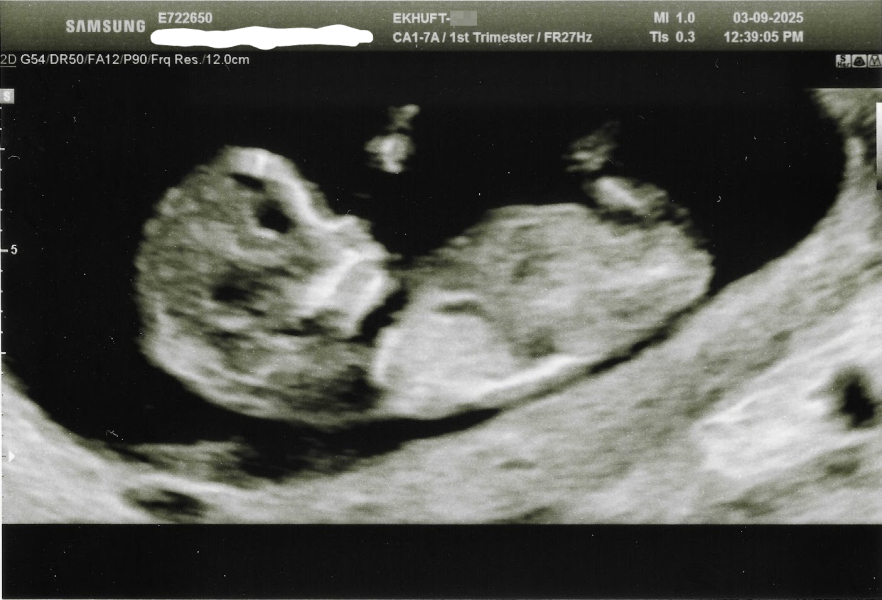

We need to save up for my last embryo to be put back, and so we just carried on trying naturally in the meantime. I then got a positive pregnancy test in July and I thought it was going to end in another loss, I was more or less expecting it at this point. However, it turns out it was the best £4k we've spent, because for the very first time ever, I got this on Wednesday! I still can't believe it!

(I was 12+3 by last menstrual period, the sonographer measured 12+1 in the scan, so I'm 12+4 today)